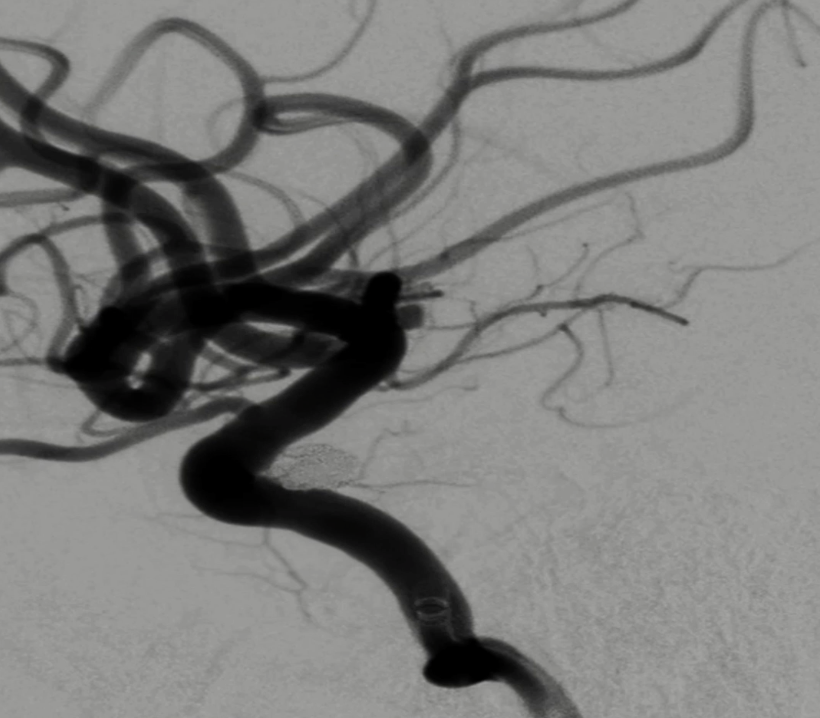

通过璞慧0.017微导管填入Target 1.5/2弹簧圈部分成篮,后释放Atlas 3.0/15支架覆盖瘤颈处,继续填入弹簧圈时微导管脱出,尝试用弹簧圈将微导管引导超选瘤腔失败。

撤出弹簧圈,Asahi 0.014微导丝引导璞慧 0.017微导管穿支架网孔进入动脉瘤内。

继续填入Target 1.5/2弹簧圈成篮,后完全释放支架,其近端位于颈内动脉分叉处,远端位于A1远端。

填入第一枚弹簧圈

通过调整栓塞微导管的张力继续填入Target 1/3弹簧圈。

术后正侧位造影:Raymond Ⅲ级

术后支架重建:支架打开良好,近端Marker位于颈内动脉分叉处